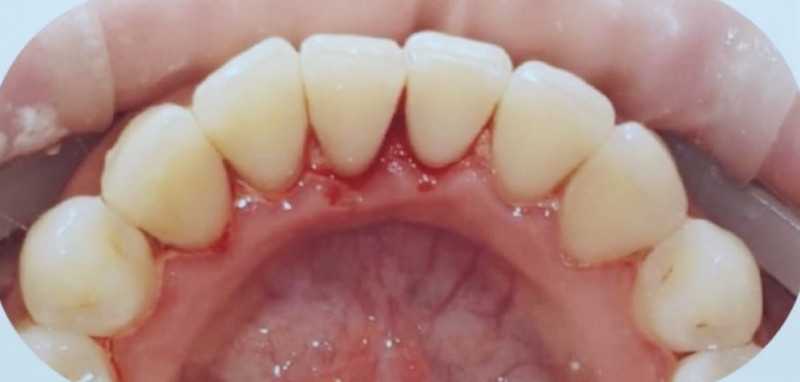

Центр стоматологии НЕБОЛЬСИН

Профгигиена

Жемчужная чистка зубов

Доктор: Евченко Надежда Владимировна